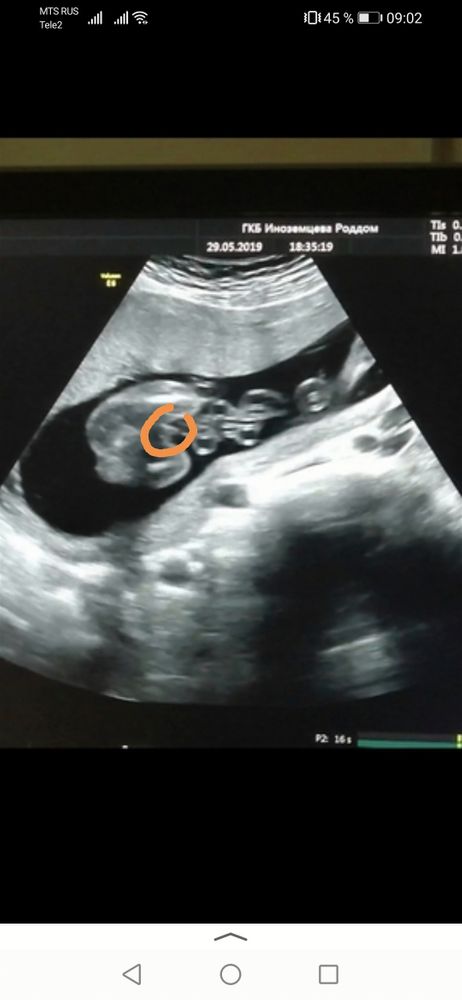

Вот у меня мальчик выглядел так в 18 недель полных.

Алина, у меня есть такие кадры-сравнение. Слева - дочь, справа - сын. Оба со стороны попы, и там, где сын, писюн не в кадре, но явно видно, что не девочка.